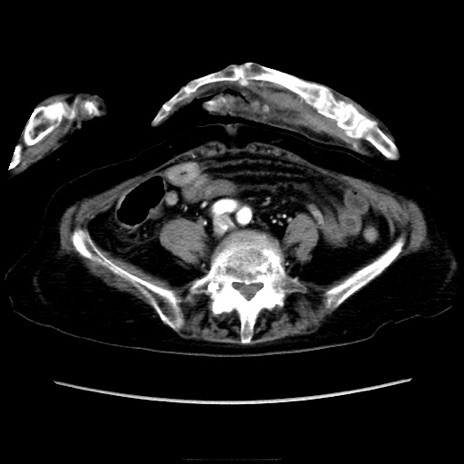

冠状断像